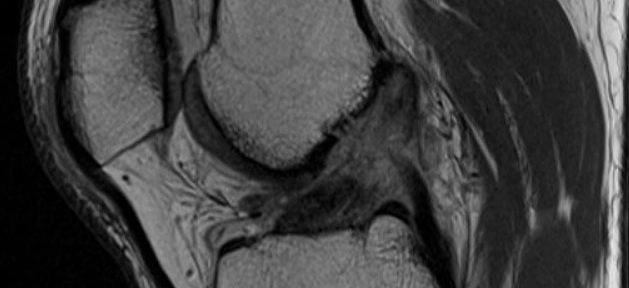

Caso 50 | Rigenerazione Naturale del LCA: Dalla Grave Rottura Ihara IV alla Perfezione Strutturale (ACLOAS 0)